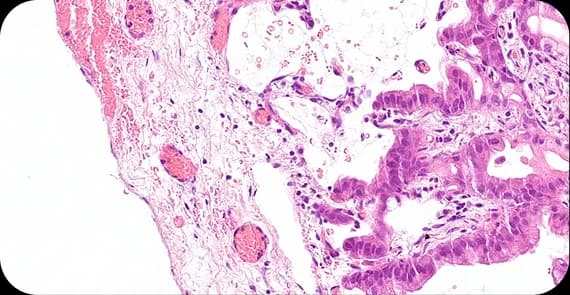

Colon cancer stages describe the extent of tumour growth and spread.

Cancer is limited to the inner layers of the colon wall.

The tumour has grown through the wall but not spread to lymph nodes.

Spread to nearby lymph nodes.

This stage refers to metastatic colon cancer, which is cancer that has spread to distant organs, such as the liver or lungs.

Colon cancer stages are crucial for determining prognosis and appropriate treatment.